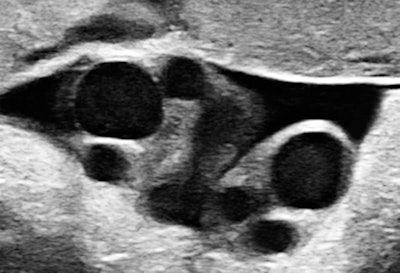

I recalled that case when I saw a primipara at 34.6 weeks, sent in because of suspected growth acceleration. A second-trimester exam had shown a normal-appearing male fetus and established the dating. The unexpected finding was a double-loop nuchal cord with some lengthy segments of diminished spiraling of the arteries. Multiple loops are generally thought to convey an increased chance of complications.

All images courtesy of Dr. Jason Birnholz.

There are high-velocity spicules in the tracing. We have tended to think of these as microturbulence events, signaling the presence of surfactants in ejected lung fluid. This is unusual at the current gestational age in a male fetus, except when there has been repeated stress promoting lung maturation.We hit the panic button when we observed a lot of exaggerated head and torso movements (like aversive behavior) with a lot of mouth and tongue activity. I will leave it to you to decide what to make of fetal expression during one of the movement episodes.

Pulmonary maturation was confirmed, the patient was delivered, and the outcome was fine. Everything might have been equally fine with simple observation, but no one, including the prospective parent, thought the risk would have been warranted, even though the clues to problems were in the subjective, if not flaky, area of behavior.